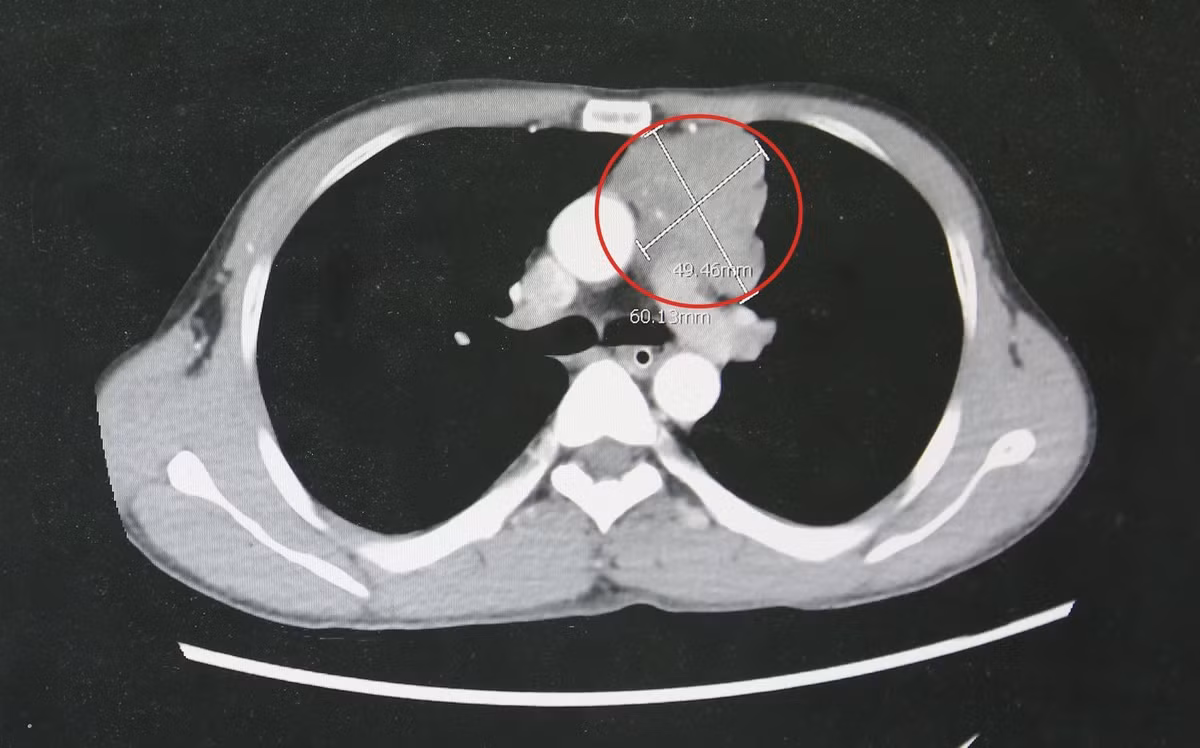

Qua thăm khám lâm sàng, cơ lực chi chỉ còn 3/5, phản xạ kém, cơ lực cổ yếu, cơ hô hấp suy giảm. Kết quả chụp cắt lớp vi tính lồng ngực phát hiện khối u trung thất trước kích thước lớn khoảng 4x6cm, xâm lấn thần kinh hoành, bên trong có vôi hóa.

Khối u tuyến ức kích thước lớn của bệnh nhân gây nhược cơ - Ảnh BVCC